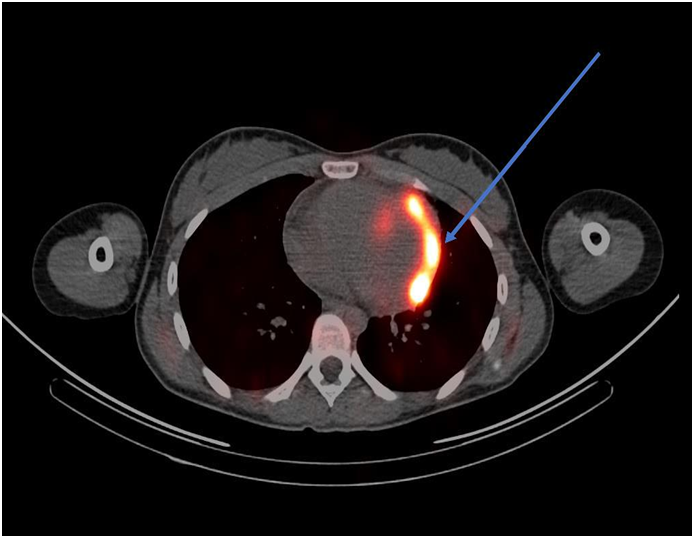

ECG revealed sinus tachycardia and right axis deviation without ST-T changes (Figure 1.). Laboratory studies, summarized in Table 1, revealed a mild normocytic, normochromic anemia and a considerably elevated serum troponin I level. Chest radiography (Figure 2) revealed a non-specific mild left perihilar/lingular area of atelectasis or infiltrate. Given her history of fever, the patient underwent technetium labeled white blood cell (WBC) scanning, prior to the onset of her chest pain, which revealed intense labeled WBC uptake at the left ventricular myocardium consistent with myopericarditis (Figure 3). A transthoracic echocardiogram (Figure 4) revealed normal right and left ventricular (left ventricular ejection fraction of 55-60 %) and a small pericardial effusion.

Figure 3 Technetium labeled WBC scan (arrow indicating significant uptake in the left ventricular myocardium).

Familial Mediterranean fever (FMF) is an autosomal recessive, hereditary, autoinflammatory disorder caused by mutations in the MEFV gene located on chromosome 16p. The disease is characterized by recurrent episodes of serositis and fever which may be accompanied by an erysipelas-like rash.3,4 FMF is most prevalent in individuals of Ashkenazi Jewish, middle eastern, Turkish and north African descent, with an estimated disease rate in these populations of around one in five hundred and a carrier rate varying between one in eight to one in four.2 FMF has also been reported in populations, such as Greek and Italian, albeit at a much lower disease prevalence and carrier state.3 Our patient presented with a six-month history of intermittent right lower quadrant abdominal pain, joint pains and high grade fevers with suspicion for appendicitis requiring an appendectomy. Finally, pleuritic-like chest pain with associated marked troponemia and a technetium labeled WBC scanning revealing neutrophilic inflammation in the left ventricular myocardium and overlying pericardium.

With regard to radionuclide scanning, gallium-67, indium-111, and technetium-99m have been used. Approximately 90 % of gallium-67 is retained in plasma after intravenous injection and almost all of it is bound to transferrin.12 Gallium-67 also binds to lactoferrin which has high levels in infectious foci.14,15 In myopericarditis, gallium-67 single photon emission commuted tomography (SPECT) scan usually reveals significant uptake in the myocardium and pericardium; however, use of gallium-67 over time has diminished because of its lack of specificity.14 WBC scanning to diagnose myopericarditis involves using the patient’s white blood cells, usually neutrophils, radiolabeled with technetium-99m or indium-111 antimyosin antibody and injected intravenously back into the patient, followed by single photon emission commuted tomography.15 As with the gallium scan, the WBC scan will usually reveal significant activity in the myocardium and pericardium on SPECT in patients myopericarditis.16 Both techniques of WBC scanning have been extensively used, specifically the indium-111 antimyosin antibody WBC scan. The sensitivity and negative predictive value of the indium-111 antimyosin antibody in diagnosing myocarditis were 91-100 % and 93-100 % in one study.17 The use of indium-111 antimyosin antibody scan has decreased over time because of radiation exposure and the requisite 48-hour delay in obtaining the imaging results.16 Our patient underwent a technetium-99m labeled WBC scan which revealed intense abnormal uptake in the left ventricular myocardium, with a noted small pericardial effusion.